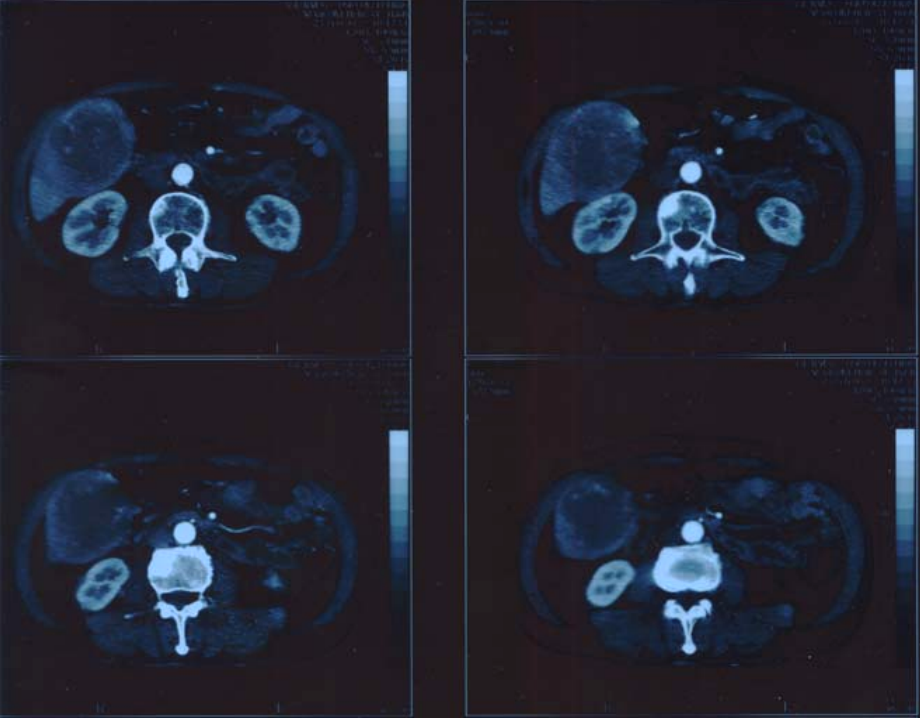

Figure3